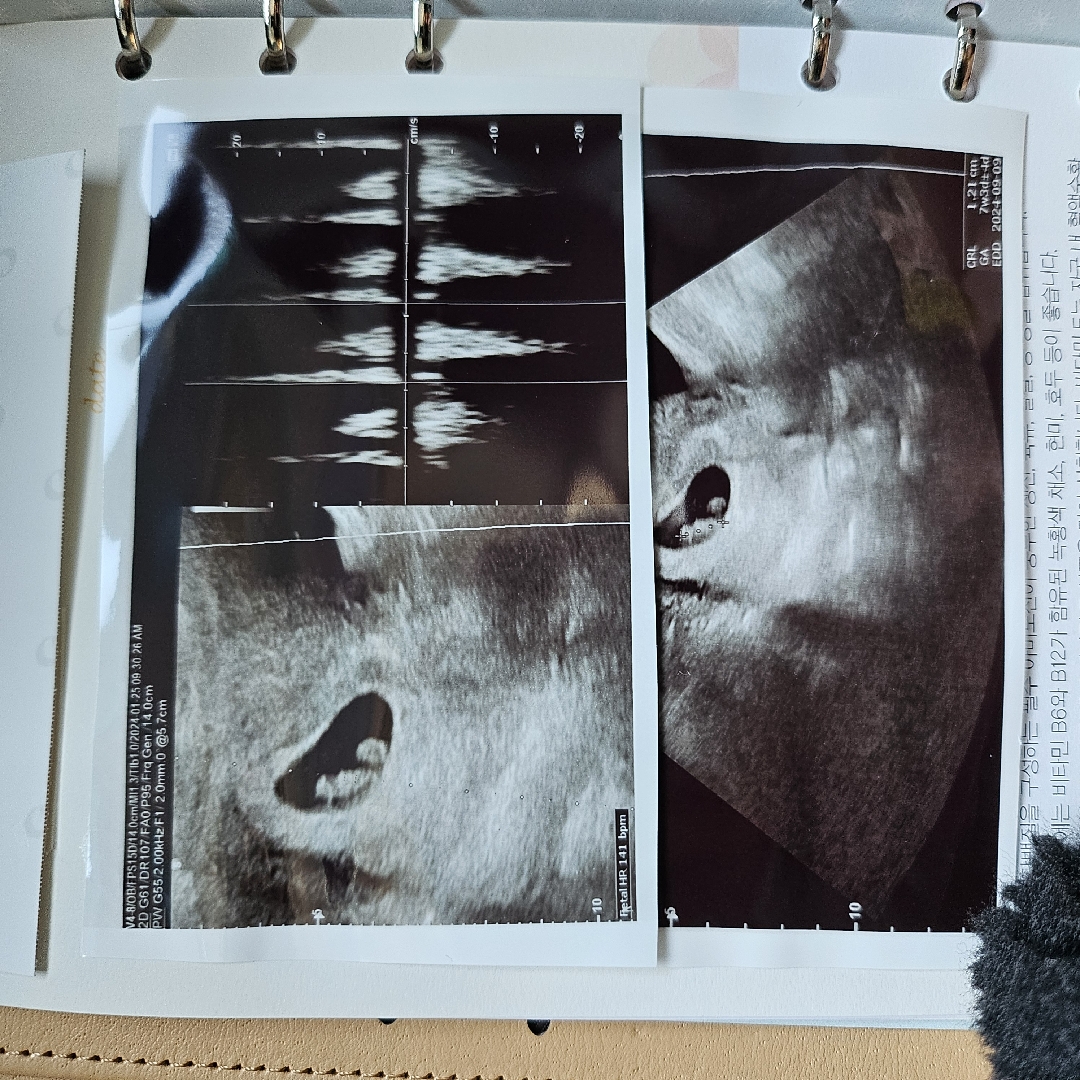

7주 4일

네이버기준에서 -1일 차이나요 이제 8주 들어가는데 4주에서 8주까지 관리가 중요하다며.. 심장듣는데 너무미안하더라구요 눈물이 콰르르.. 그래도 잘자라주고있어 너므 고마운 하루였어요